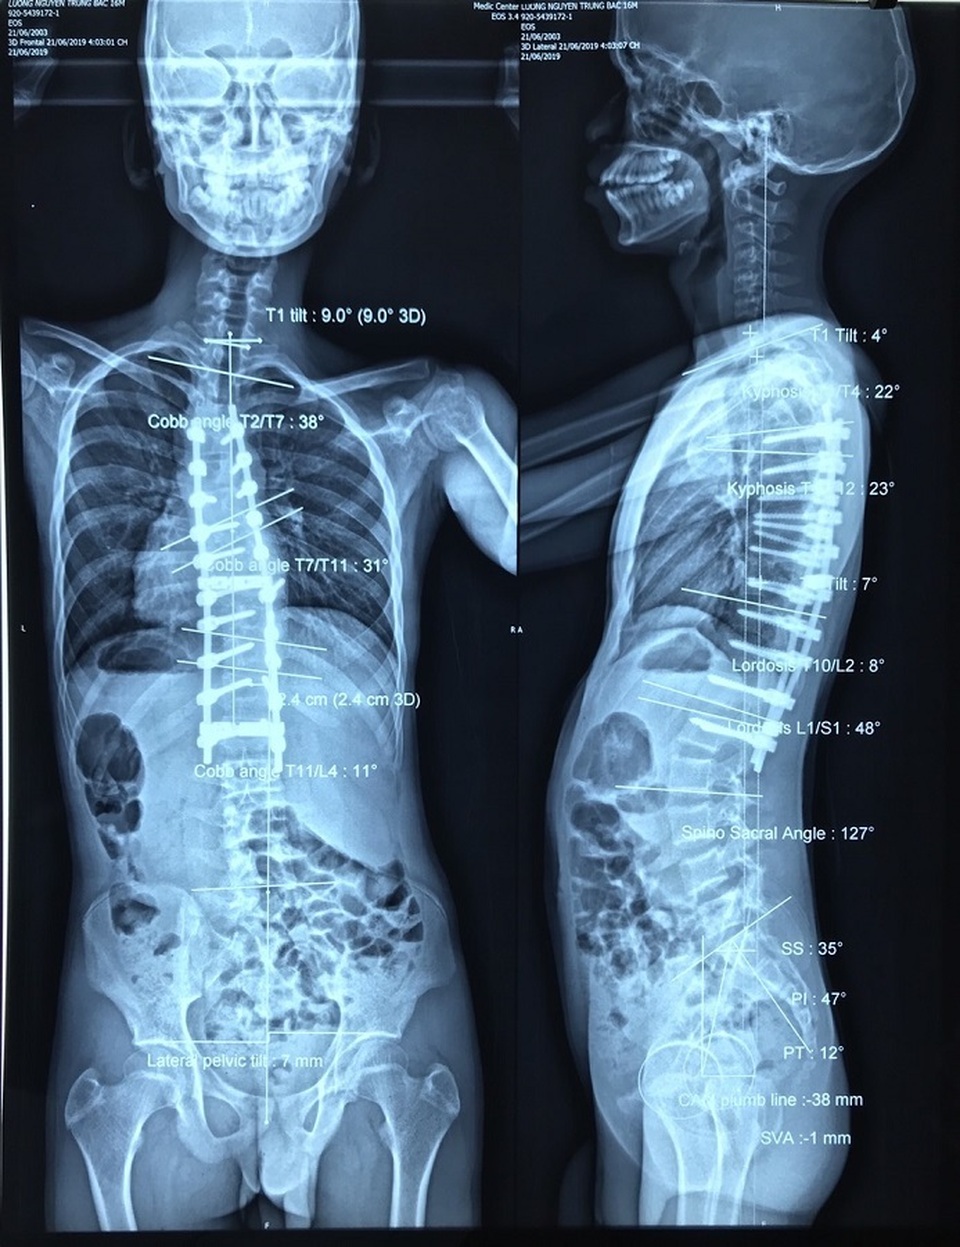

Các bác sĩ đã đặt nẹp vít nắn cột sống về vị trí bình thường

Với sự chung tay của cộng đồng và nỗ lực của các bác sĩ, nam thanh niên đã được phẫu thuật đặt nẹp vít thành công, nắn cột sống trở về vị trí bình thường. Ngày 25/6, gia đình cho biết, sức khỏe của Trung B. đã ổn định, thoát khỏi tình trạng, đau, khó thở, tê yếu chân, có thể đi lại bình thường.